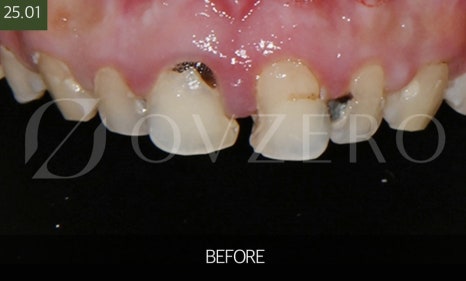

지르코니아 크라운이 필요한 상황

지르코니아 크라운은

치아를 “전체적으로 보호해줘야 할 때”

선택하는 치료입니다.

예를 들면 충치가 많이 진행되어

레진이나 인레이로는 강도가 부족한 경우,

치아가 깨지거나 금이 가서

씹을 때 통증이 반복되는 경우,

신경치료를 받아 치아가 약해진 경우에

주로 크라운 치료를 진행하게 됩니다.